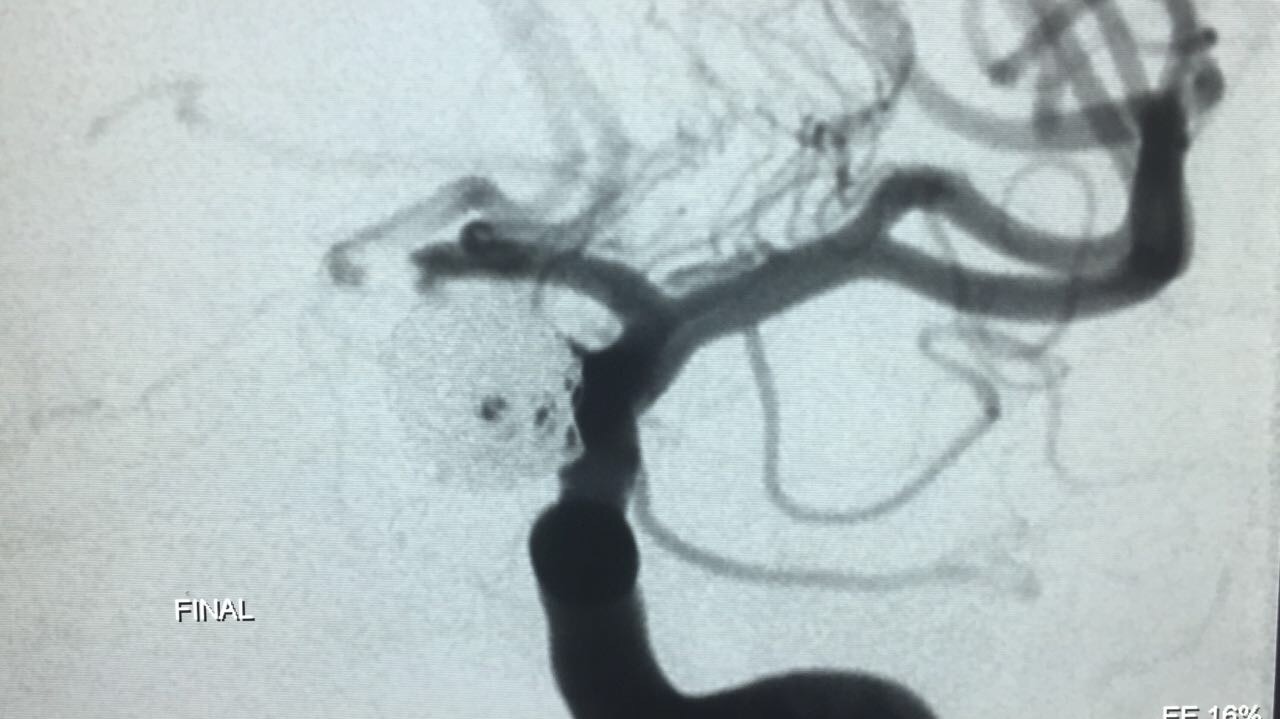

Paciente foi então encaminhada ao setor de hemodinâmica sendo realizado Angiografia cerebral Digital e evidenciado aneurisma de segmento oftálmico da artéria carótida interna esquerda. Realizado embolização do aneurisma com microespirais, sem intercorrências. A paciente permanece em bom estado geral e neurológico recuperando em pós operatório imediato.